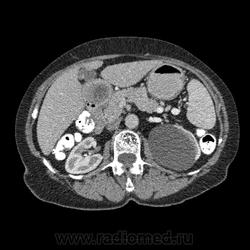

Впечатление, что дуля эта вне головки п.ж., интрамурально в луковице, что ли... тогда возможно GIST, но надо дайком. Утолщение подслизистой в антральном отделе желудка, не удается проследить переход от желудка к 12-перстной((. Внутрипросветно/внутристеночно - не разобрать. 1 фаза?

Клинику! Есть ли признаки высокой тонкокишечной непроходимости, что при ФЭГДС в 12-перстной - туда удалось пройти или нет? ААА! Одни вопросы))))

В-общем, варианты такие без дайкомов: пролапс слизистой в 12перстную, безоар, внутрипросветный дивертикул, гастроинтерстинальная опухоль. И большие сомнения, что это в головке п.ж. - оно отделено от неё тонким слоем жировой клетчатки

Фаз было 3. Видео не выставлял прошлый раз пришел ответ из сайта что видео не работает на сайте Идет накопление контраста в нативе в центре +2+4 по периферии +32+34 .в артериальную +20 и +65 +70 соответственно.

Что оно копит - бог с ним... если это пролапс слизистой, то суммация стенок. Безоар бы не копил. Напрягает отек слизистой в антрале... Это должно быть скорее внутри просвета кишки, т.к. оттесняет газ в 12-перстной на периферию. Без дайкомов больше ничем не могу, извините. Подождём мнения коллег.

Как мне видится - пролапс слизистой желудка в 12-перстную. А мнения коллег что-то нетути...

А что растет из левой почки? Может оно же и желудок сдавливает?

Это расширение всей 12- перстной кишки (стаз).